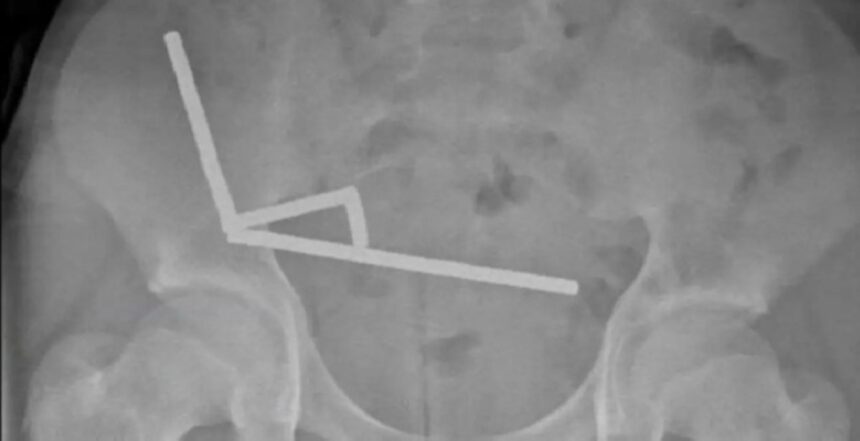

وبحسب تقرير لموقع ScienceAlert، فإن الصبي نُقل إلى مستشفى «تاورانغا» وهو يعاني من آلام شديدة في البطن، ليكتشف الأطباء لاحقًا وجود مئات المغناطيسات المعدنية التي التصقت ببعضها داخل الأمعاء، مسببة انسدادًا خطيرًا وتسربًا في الأنسجة الداخلية.

وأوضح الجراحون أن المغناطيسات القوية التصقت بجدران الأمعاء من الداخل، ما أدى إلى انقطاع تدفق الدم وتمزق أجزاء دقيقة من الجهاز الهضمي. ورغم صعوبة الحالة، تمكن الفريق الطبي من إنقاذ حياته بعد استئصال جزء من الأمعاء التالفة.